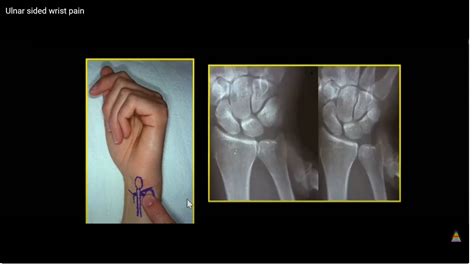

Diagnosing Outer Wrist Pain

Diagnosing the cause of outer wrist pain involves a thorough medical history, physical examination, and diagnostic tests. Your healthcare provider may perform the following:

• Physical examination to assess the range of motion, strength, and tenderness in the wrist

• Imaging tests, such as X-rays, MRI, or CT scans, to visualize the bones and soft tissues